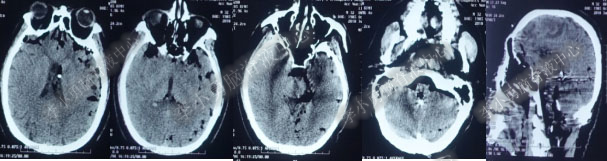

第4次出院后11天即2018年4月15日(分流术后284天,第2次的软性内镜术后179天),因引流管堵塞第5次住入该院,引流管内白色絮状物增多,引流管被堵塞。入院当天复查头部CT(图-10)显示脑室系统仍扩张。

图-10:2018年4月15日头部CT

第5次入院第2天即2018年4月17日,脑室腹壁外引流管堵塞,意识恶化,复查头部CT(图-11)示全脑室系统又较前扩大。当天急诊行左侧脑室穿刺外引流术。脑脊液化验外观黄色浑浊,并且送培养,结果是无菌生长。

图-11:2018年4月17日头部CT脑室扩张又加重

第5次入院第3天即2018年4月18日术后复查头部CT(图-12)显示脑室系统扩张较前好转。

图-12:2018年4月18日头部CT

第3次软性内镜术后第6天即2018年4月24日复查头部CT(图-13)脑室系统仍扩张。

图-13:2018年4月24日头部CT